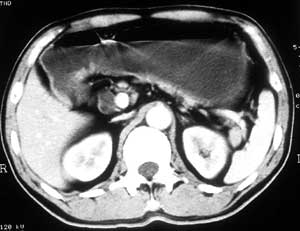

患者,男,57岁,梗阻性黄疸10余天。

这个病例胰头无明显增大,胆总管扩张明显而肝内胆管扩张更不明显,病程较短,

注意到十二指肠乳头明显突出,但尚光滑。分析以下可能性:

1、十二指肠乳头本身的病变,如乳头炎症;

2、急性乳头水肿,胆总管下端结石排石后乳头水肿;

3、壶腹部胆总管下端肿瘤累及十二指肠乳头。

十二指肠乳头粘膜慢性非特异性炎症